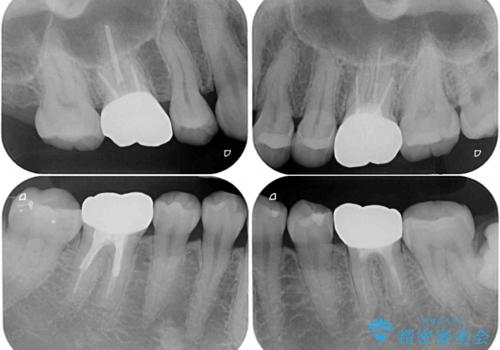

- 奥歯の銀歯が外れたことをきっかけに、全ての銀歯をセラミックに替えたいとのことで来院された患者様です。

第一大臼歯4本と、メタルインレーが装着されている2歯をセラミッククラウンならびにセラミックインレーにて補綴治療・修復治療を行うこととしました。

口腔内から、土台も含め銀歯がなくなったことでメタルフリーとなりました。